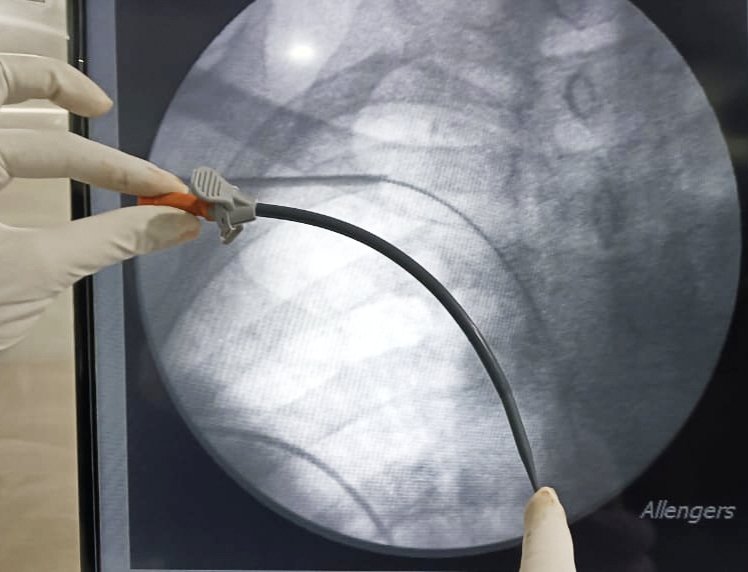

60/f

right IJV HD cath & TCC 1 yr back

Left elbow AVF primary failure

Now created right BV AVF

Soon got Right UL edema

VenoGm - stenosis at innominate

Plasty done > adequate flow> edema gone > discharge > AVF can be used now 😊

#interventionnephrology #nephrologistincathlab